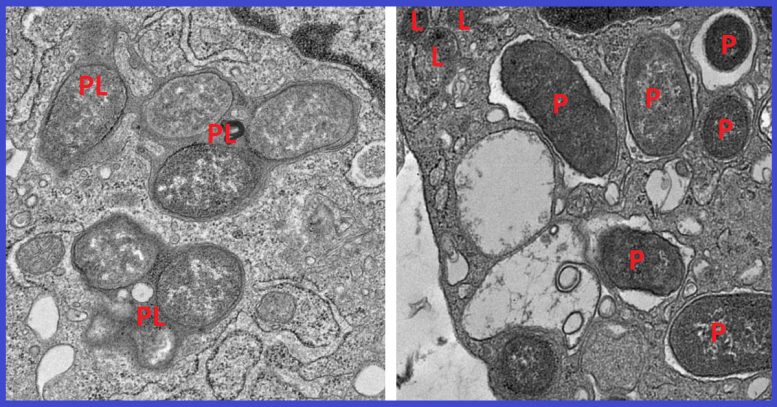

Using a powerful machine learning tool, the researchers analyzed thousands of macrophage gene expression patterns from colon tissue affected by IBD and from healthy colon tissue. They identified a macrophage gene signature consisting of 53 genes that reliably separates reactive, inflammatory macrophages from tissue-healing macrophages.

One of these 53 genes encodes a protein called girdin. Further analysis revealed that in non-inflammatory macrophages, a specific region of the NOD2 protein binds to girdin. This suppresses runaway inflammation, clears harmful microbes, and allows for the repair of tissues damaged by IBD. But the most common Crohn’s disease mutation to the NOD2 gene deletes the section of the gene that girdin would normally bind to. This results in a dangerous imbalance between inflammatory and non-inflammatory macrophages.

The researchers then confirmed the importance of the interaction between NOD2 and girdin by comparing mouse models of Crohn’s disease lacking the girdin protein to those with girdin intact. They found that mice without girdin suffered an imbalance in their gut microbiome and developed inflammation of the small intestine. They often died of sepsis, a condition in which the immune system mounts an excessive response to an infection, causing inflammation throughout the body and damage to vital organs.